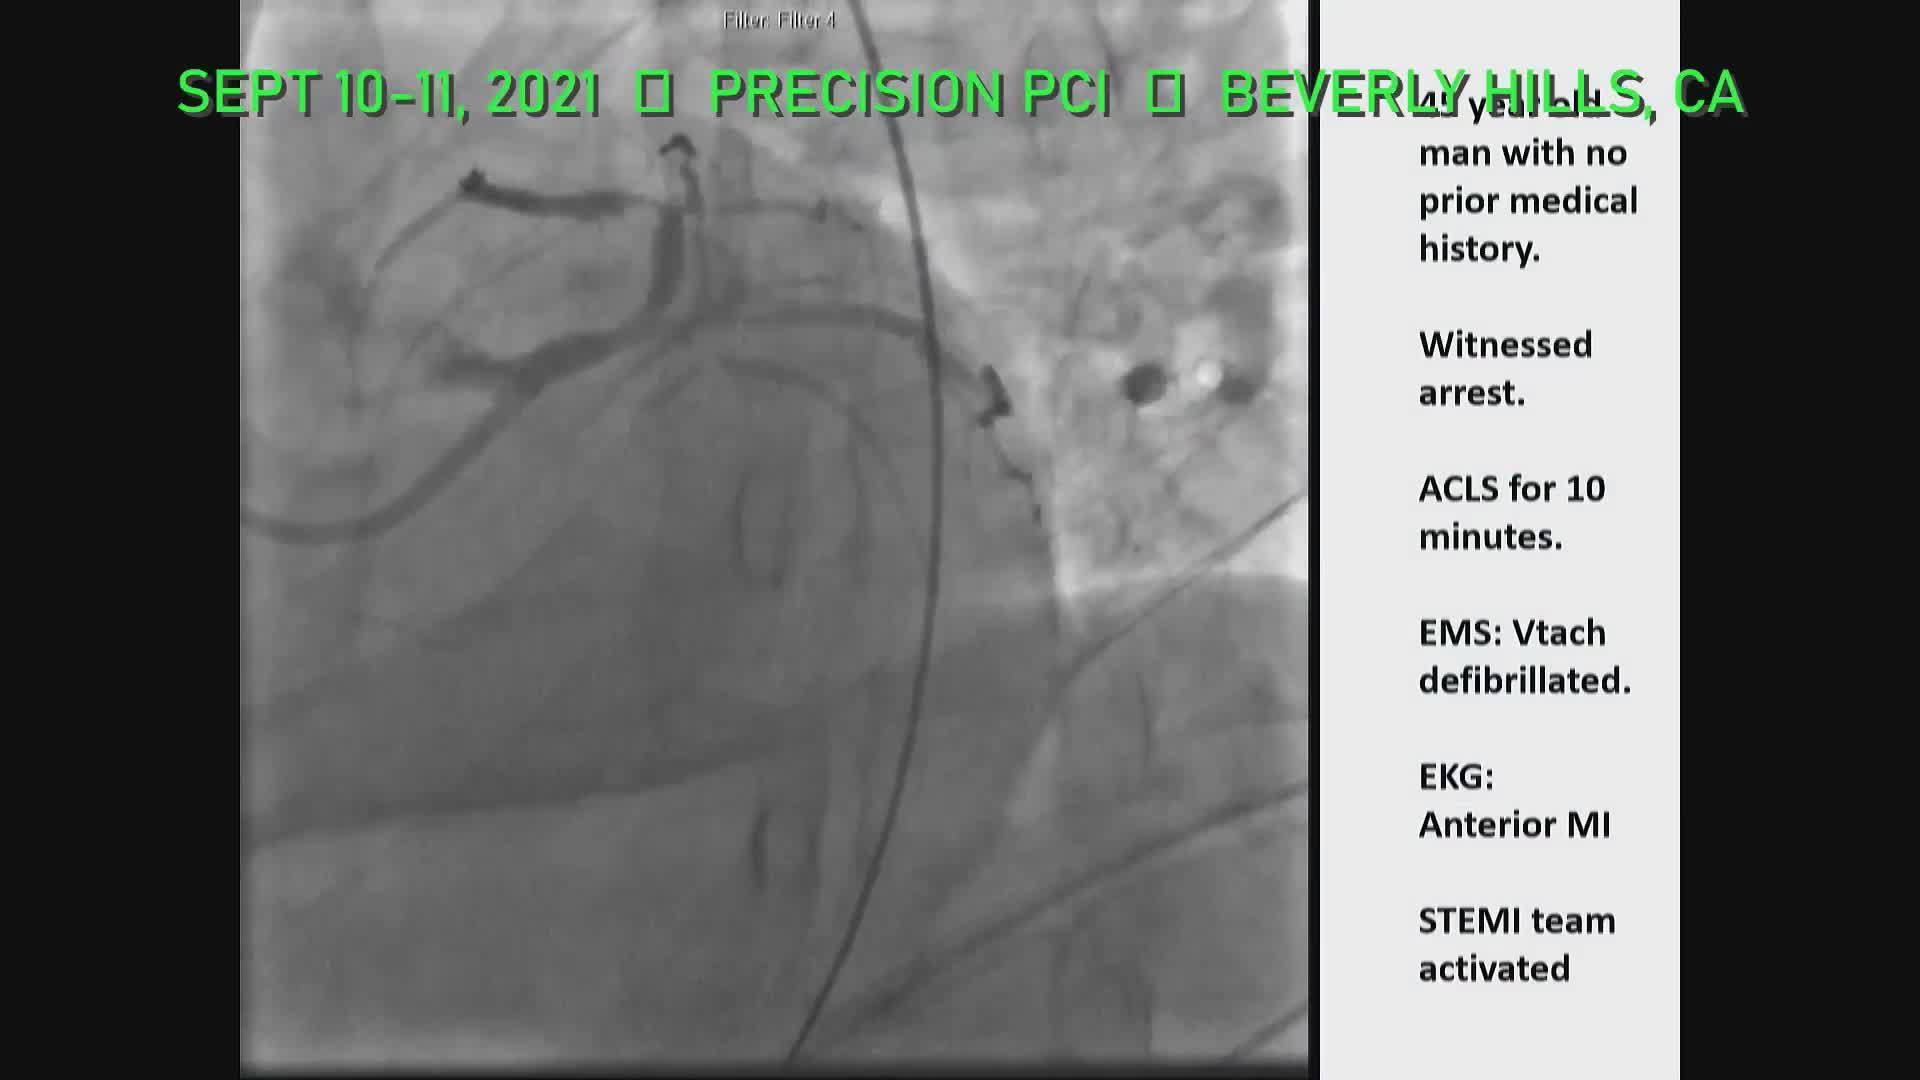

PRECISION PCI - 10th Sept 2021

PRECISION PCI - 11th Sept 2021